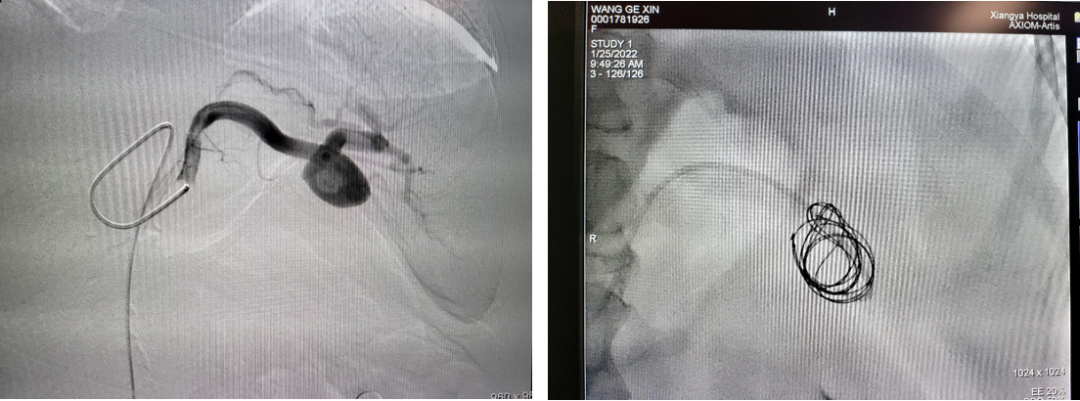

病例2 分支栓塞+瘤腔栓塞

3

病例3 瘤腔栓塞加胶填充

4